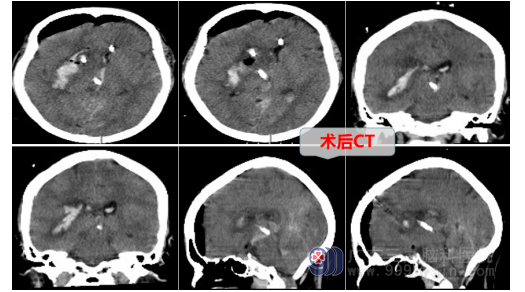

神经外十科医生在了解和明确张阿姨的病情后,当机立断,争分夺秒,迅速完善术前准备工作,急诊为张阿姨行右侧基底节区血肿清除+脑室外引流+气管切开术,术中可见脑组织压力高,导航定位血肿位置后,医生进行微创手术,将球囊逐渐扩开脑组织并置入套筒,在神经内镜下取出大量暗红色血块,将患者脑内血肿清除干净。

术后张阿姨的情况逐渐好转,从入院时的重度昏迷、生命垂危状态,到现在一侧肢体可以自主活动,甚至有时叫张阿姨握住医务人员的手,也可以简单遵嘱,一切都在往好的方向发展。